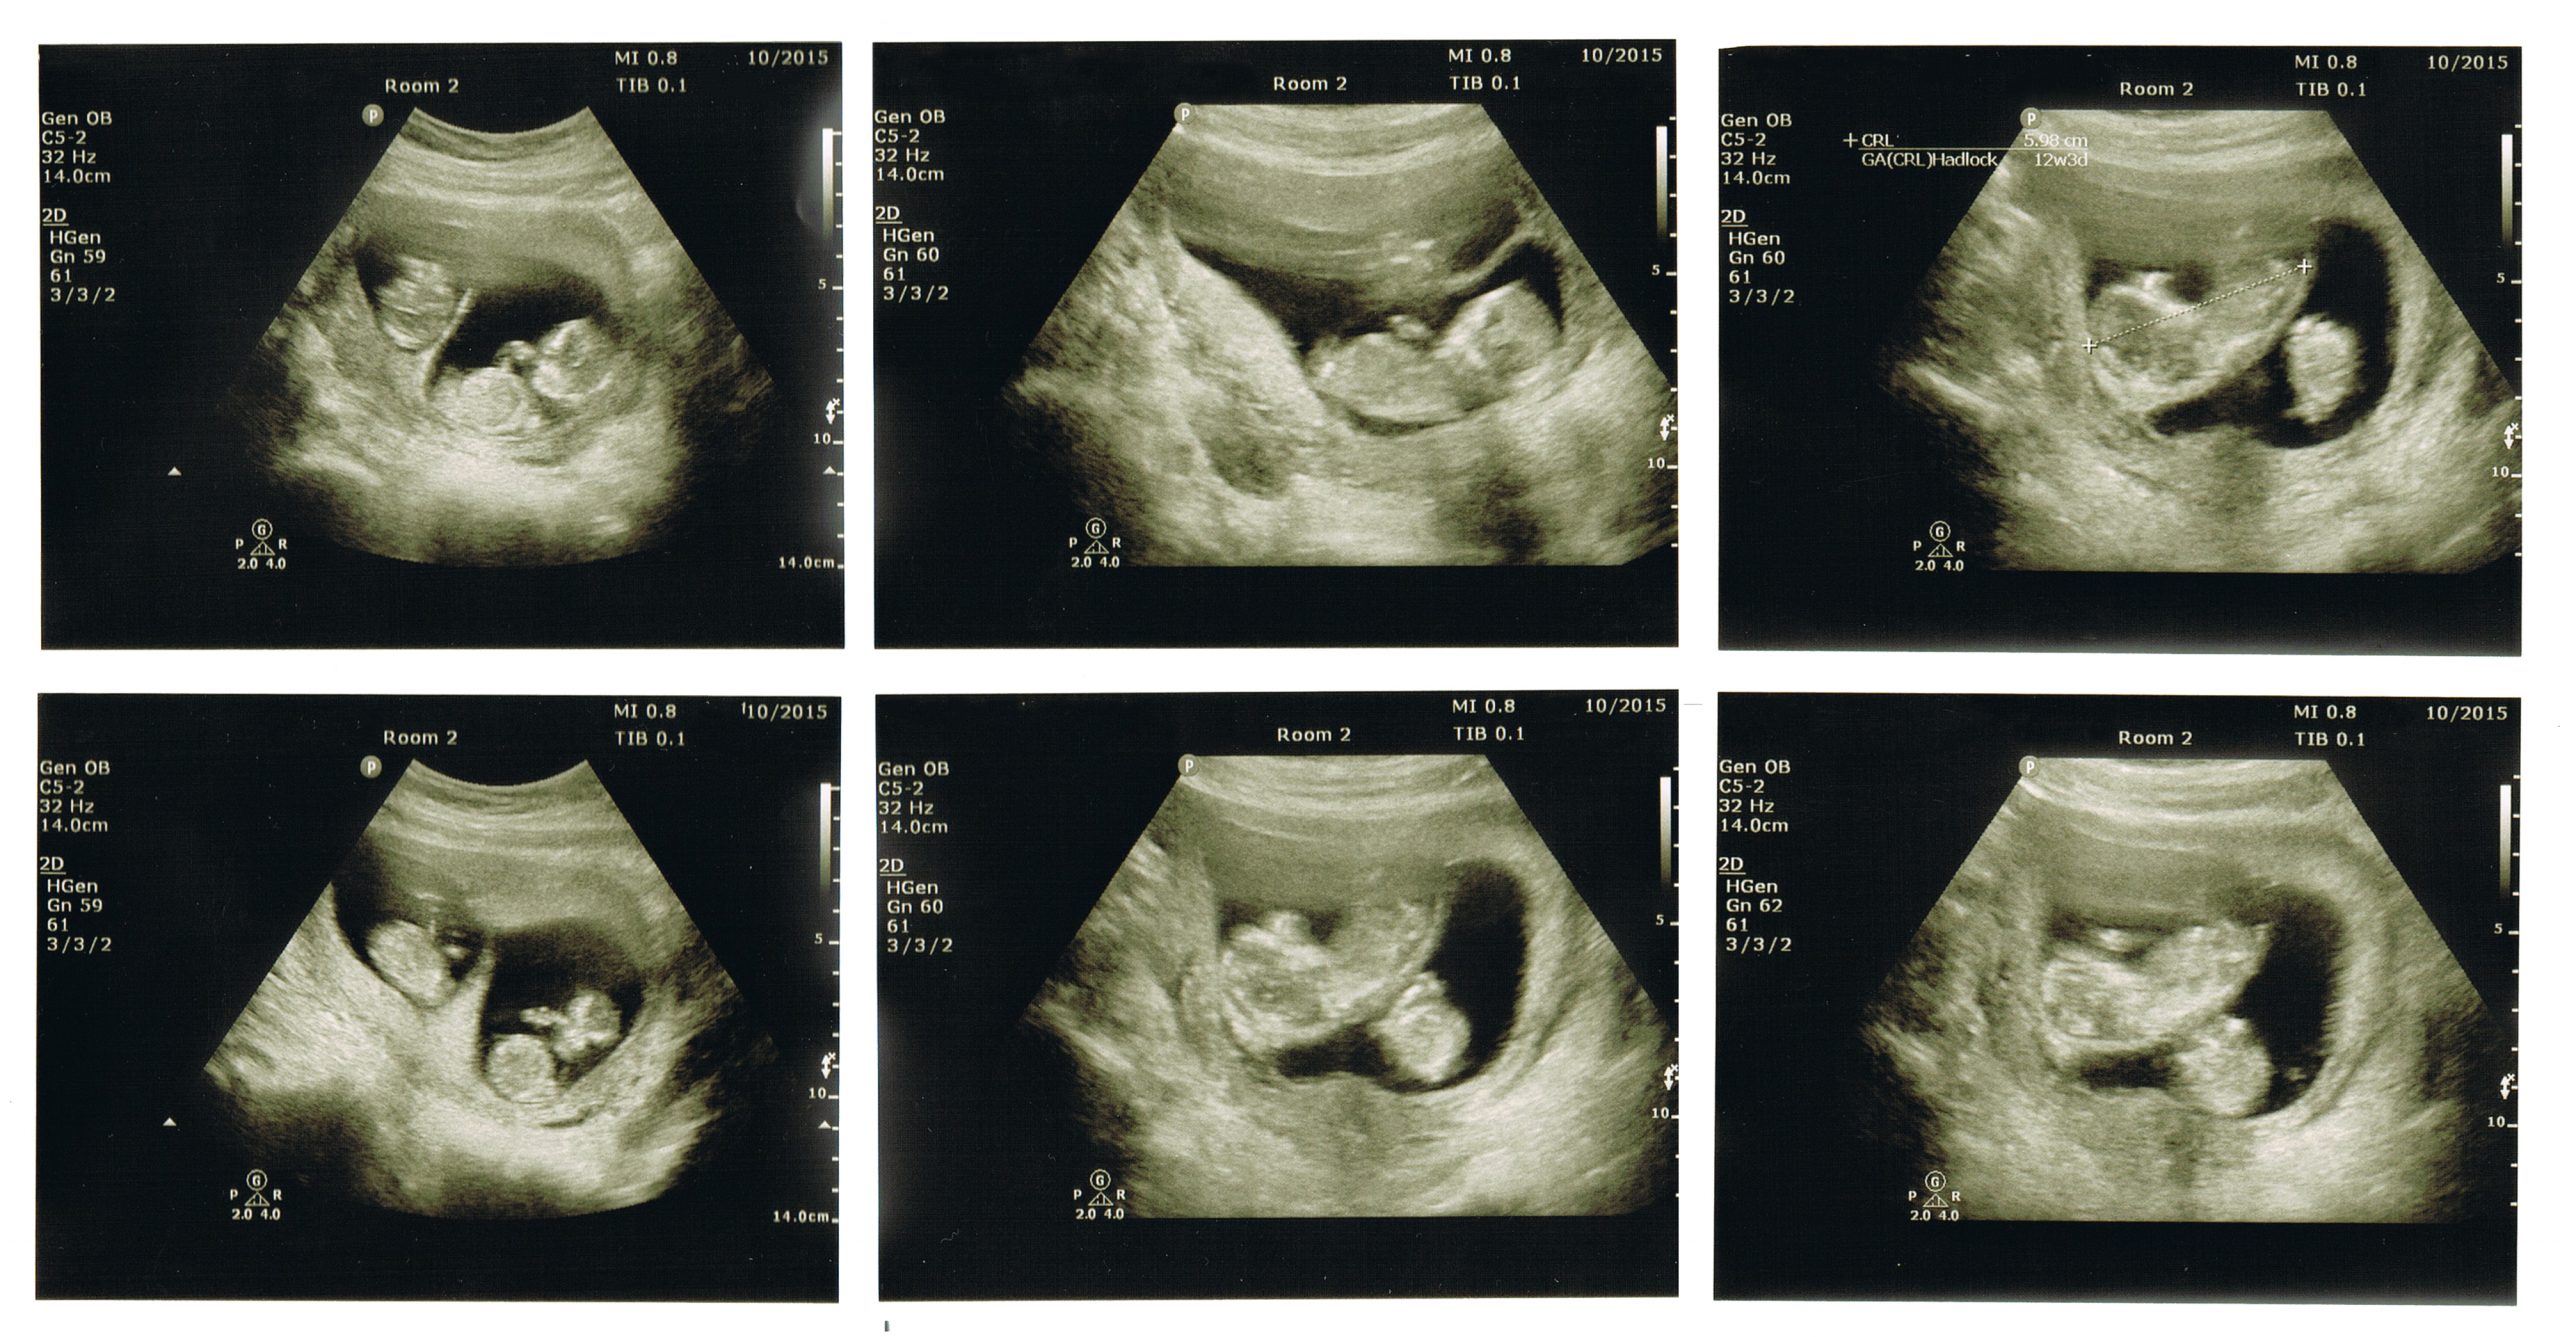

Близнецы на УЗИ в 12 недель: что нужно знать

На данной странице вы найдете фотографии близнецов на УЗИ в 12 недель, а также полезные советы для будущих мам, ожидающих двойню. Узнайте, что ожидать на этом этапе беременности и как правильно подготовиться к УЗИ.

Определение многоплодной беременности по УЗИ

Двойня. Мальчики. УЗИ.

Многоплодная беременность на УЗИ. Близнецы.

Узи двойни, 10-11 недель - Twins Ultrasound (10-11 weeks)